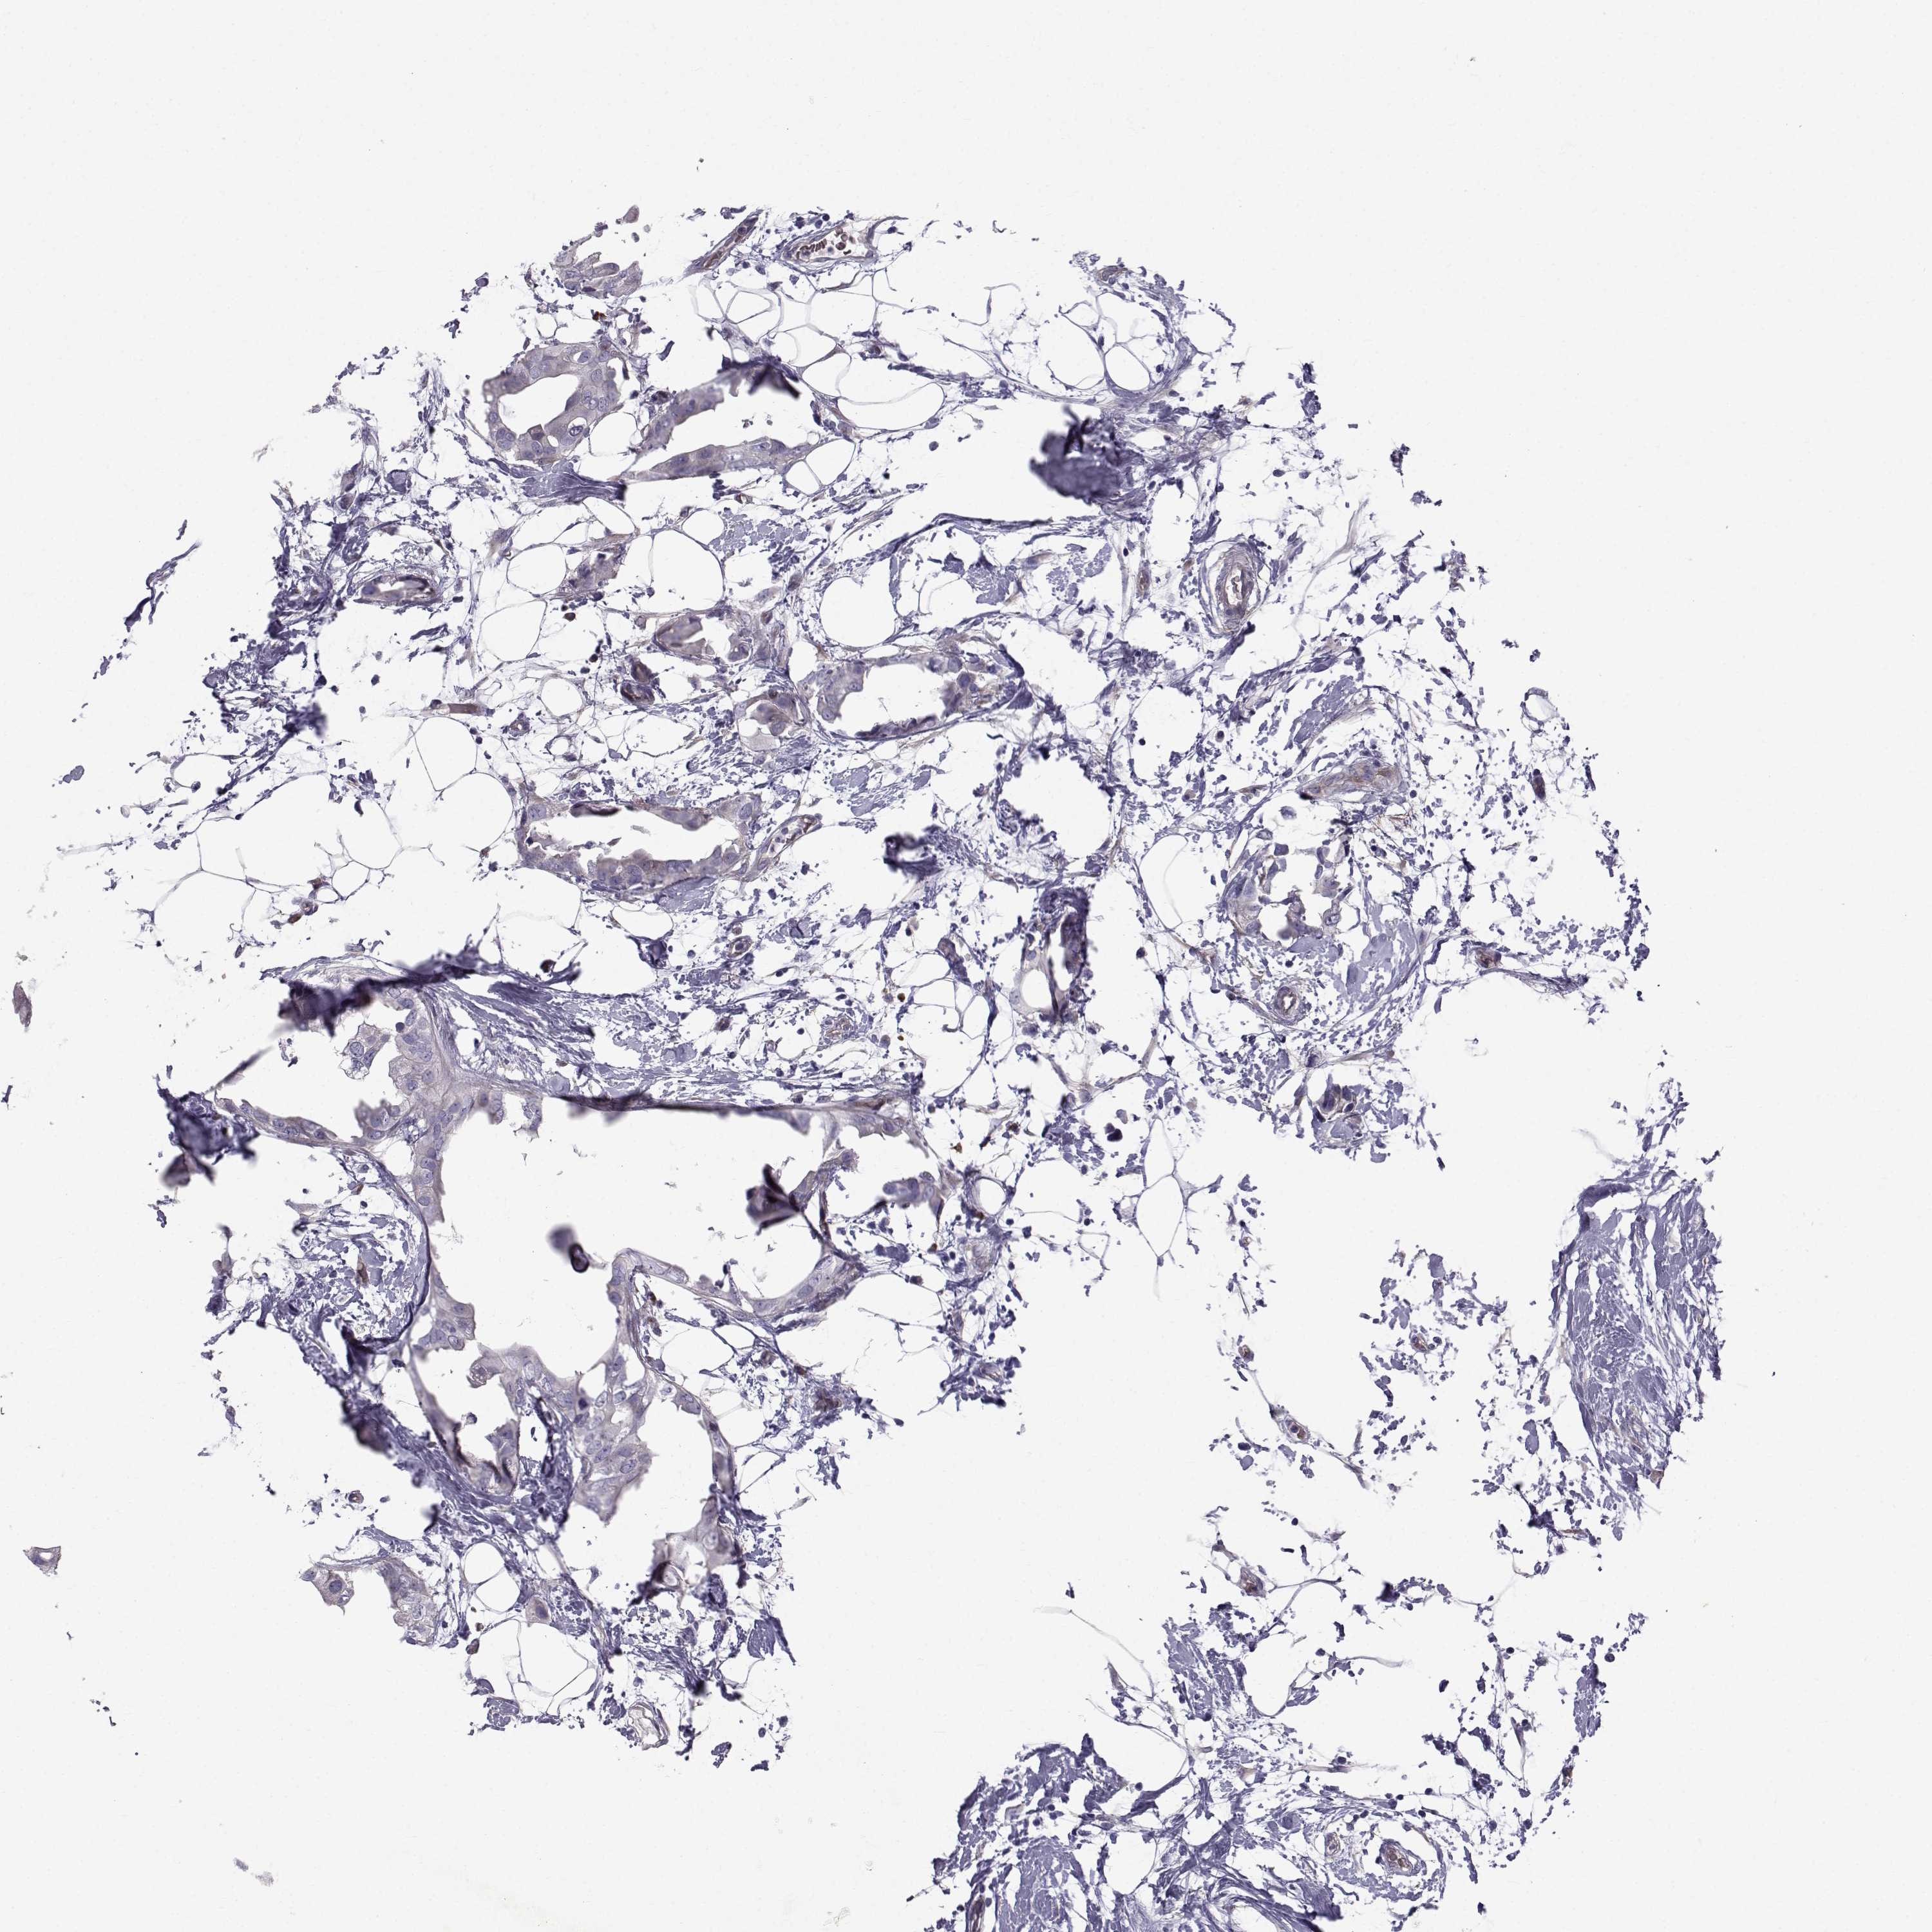

CANCER BREAST CANCER Show tissue menu

Breast cancer

Human cancer